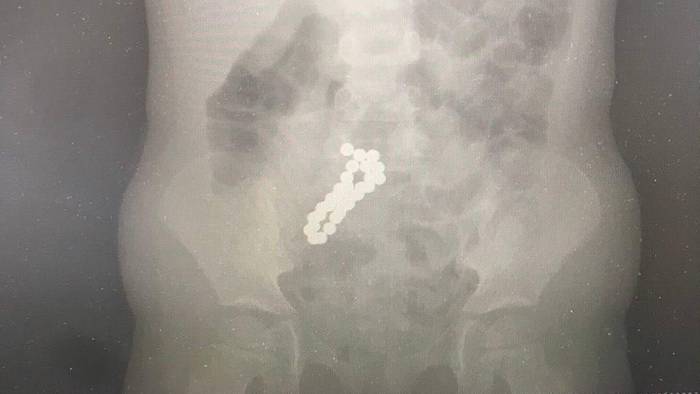

Фото: Пресс-служба Министерства здравоохранения Московской области

Специалисты Московского областного центра охраны материнства и детства (МОЦОМД) достали из кишечника четырехлетней девочки 30 магнитов. Об этом во вторник, 3 марта, сообщили в пресс-службе регионального министерства здравоохранения.

— Врачи провели исследования и обнаружили в тонком кишечнике девочки 30 магнитных шариков диаметров по десять миллиметров. Магниты извлекли лапароскопически — через маленькие проколы, — объяснил врач детского хирургического отделения Сергей Борисов.

Операция прошла успешно, состояние ребенка сразу же улучшилось. Сейчас девочка уже лечится дома, уточнили на сайте ведомства.